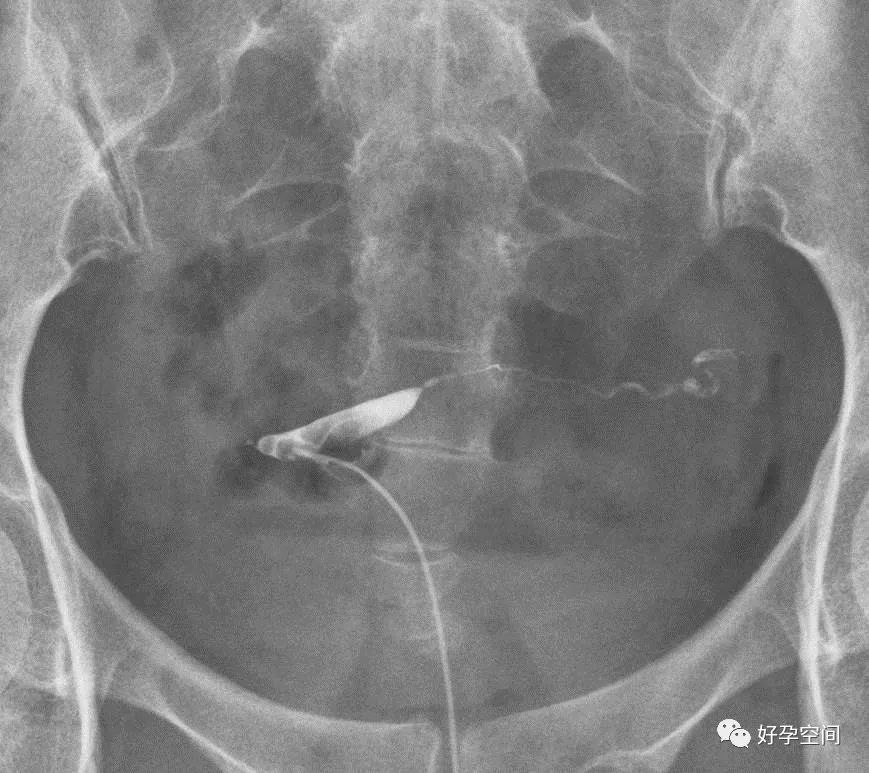

子宫相